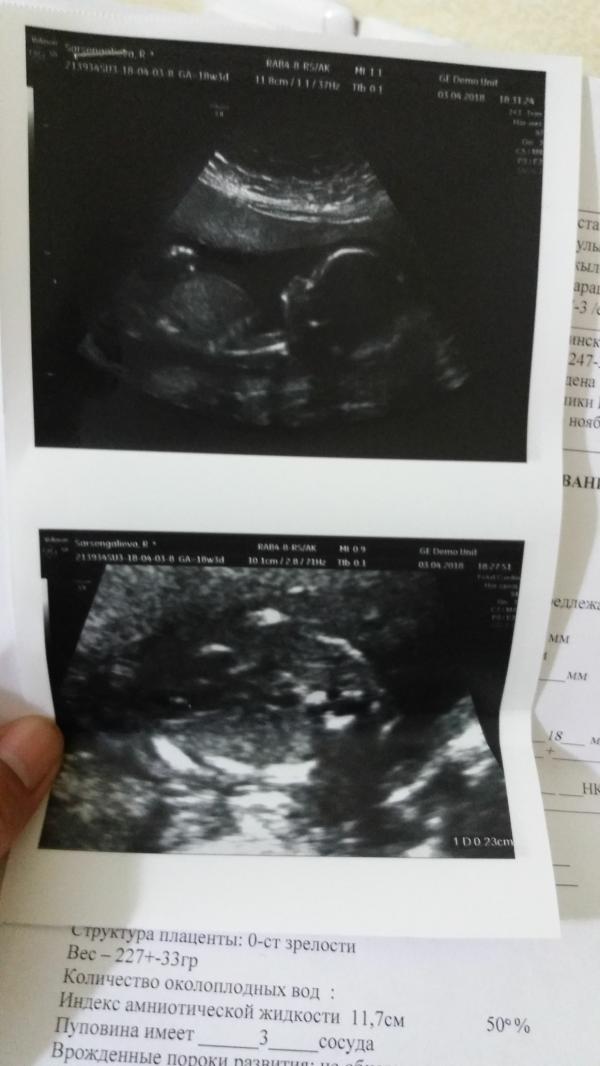

Первая фото моей малышки. Все хорошо ин ша Аллаh. Только не смогли узнать пол ребенка. Мы ножки не открываем.😊мы любим тебя малыш.